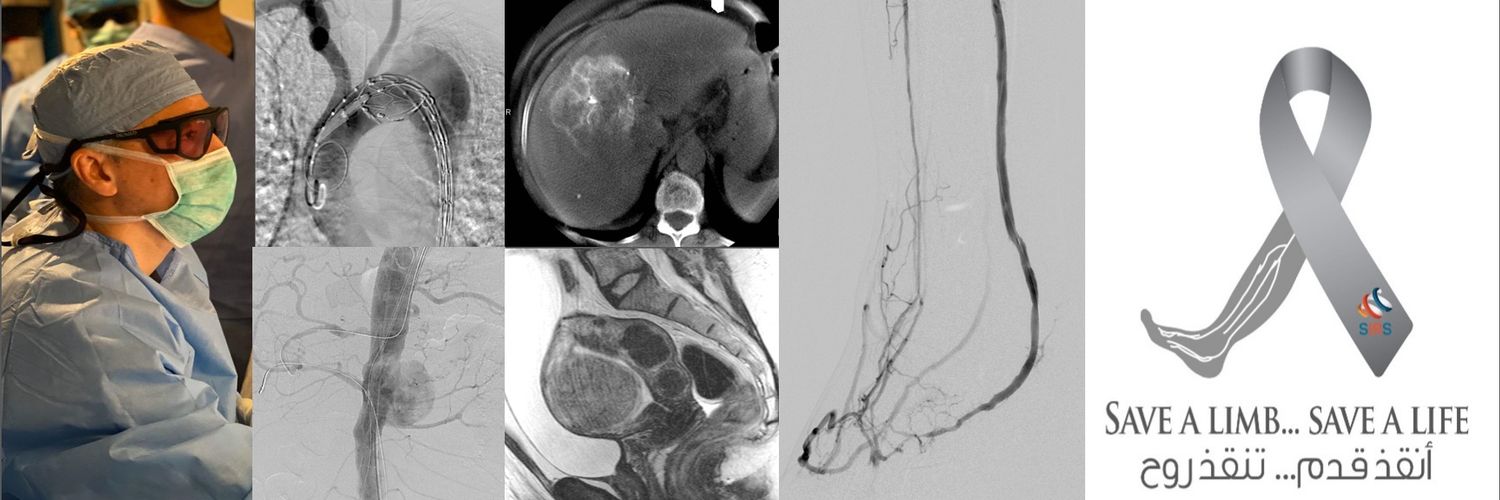

قبل 55 سنة ، في 16 يناير 1964 ، قام طبيب الأشعة التداخلية تشارلز دوتير بأول توسيع بالقسطرة لضيق شريان الفخذ، لإمرأة عمرها 82 سنة وأنقذ ساقها من البتر

For whom who don't know or forgot that IR invented percutaneous angioplasty 55 years ago, in January 16,1964 Interventional Radiologist Charles Dotter performed the first catheter angioplasty of a stenosis of SFA in an 82-yr-old woman and saved her leg amputation @sirs_ksa